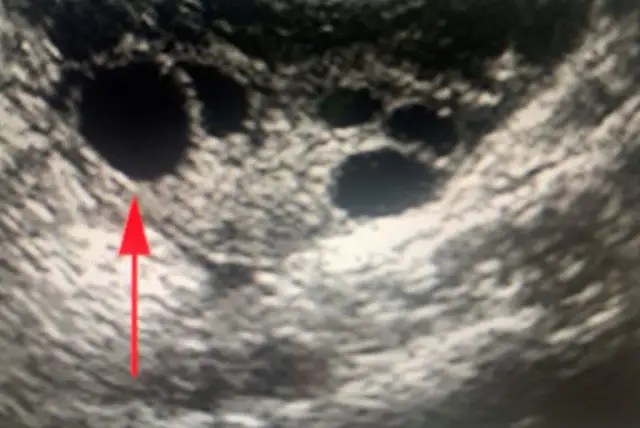

Jeśli mówimy o braku owulacji, nie sposób nie wspomnieć o Zespole Policystycznych Jajników (PCOS). To bez wątpienia najczęstsza przyczyna anowulacji, dotykająca około 5-10% kobiet w wieku rozrodczym. PCOS charakteryzuje się zaburzeniami hormonalnymi, takimi jak podwyższony poziom androgenów (męskich hormonów), insulinooporność oraz obecność licznych pęcherzyków na jajnikach (widocznych w USG), które nie dojrzewają prawidłowo i nie uwalniają komórki jajowej. To właśnie te zaburzenia sprawiają, że owulacja jest nieregularna lub całkowicie zahamowana, co znacząco utrudnia zajście w ciążę.

Monitoring cyklu za pomocą ultrasonografii (USG) jest kluczową metodą w diagnostyce anowulacji. To nic innego jak seria badań USG dopochwowych, wykonywanych w różnych fazach cyklu. Pozwala nam to na bieżąco obserwować wzrost pęcherzyków jajnikowych, ocenić grubość endometrium (błony śluzowej macicy) i, co najważniejsze, potwierdzić lub wykluczyć pęknięcie pęcherzyka i uwolnienie komórki jajowej. Dzięki temu możemy dokładnie ocenić, czy owulacja w danym cyklu występuje prawidłowo.